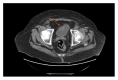

Neuroendocrine tumors rarely occur in the urinary bladder. They can be carcinomatous, subdivided into small cell and large cell pathology. Small cell carcinoma of the bladder is a rarity that may present at an advanced pathologic stage. No treatment regimens have been standardized for local or metastatic disease. Review of the recent literature shows equivalent survival data for localized disease treated with chemoradiotherapy combined with either bladder sparing surgery or radical cystectomy. Patients with significant comorbidities are an additional challenge. We report a case of poorly differentiated neuroendocrine tumor of the bladder, which could not be classified as small or large cell carcinoma, complicated by significant comorbidities. After management with transurethral resection of the tumor, adjuvant chemotherapy, and radiation, the patient is alive and asymptomatic nearly 1 year after initial TURBT with no evidence of disease recurrence.